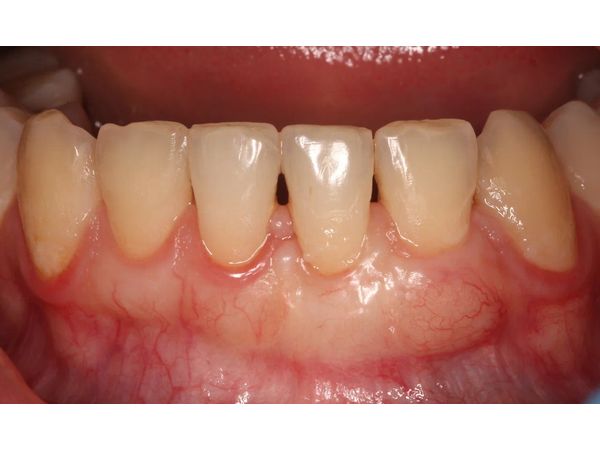

Уже через 2 недели рецессия была устранена, а сосочек восстановлен. Дубликатура сохранилась, но пациентку она не беспокоила.

Через 2 месяца женщине назначили профессиональную гигиену полости рта.